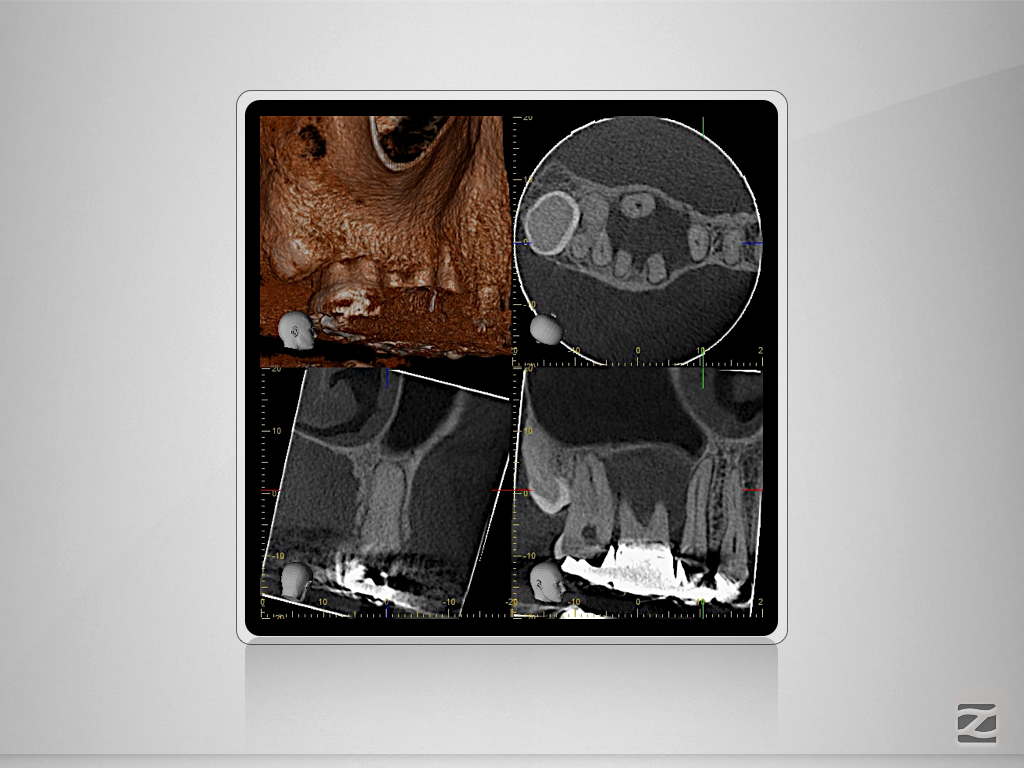

16D.007

Immer schön skeptisch bleiben 4